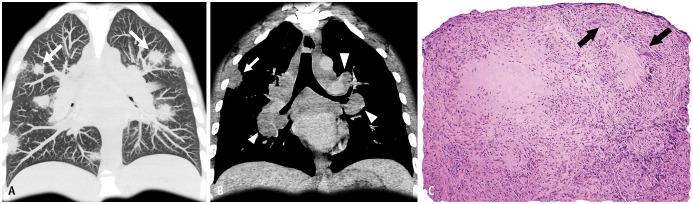

Non-infectious granulomatous lung disease represents a diverse group of disorders characterized by pulmonary opacities associated with granulomatous inflammation, a relatively nonspecific finding commonly encountered by pathologists. Some lesions may present a diagnostic challenge because of nonspecific imaging features; however, recognition of the various imaging manifestations of these disorders in conjunction with patients' clinical history, such as age, symptom onset and duration, immune status, and presence of asthma or cutaneous lesions, is imperative for narrowing the differential diagnosis and determining appropriate management of this rare group of disorders. In this pictorial review, we describe the pathologic findings of various non-infectious granulomatous lung diseases as well as the radiologic features and high-resolution computed tomography imaging features.